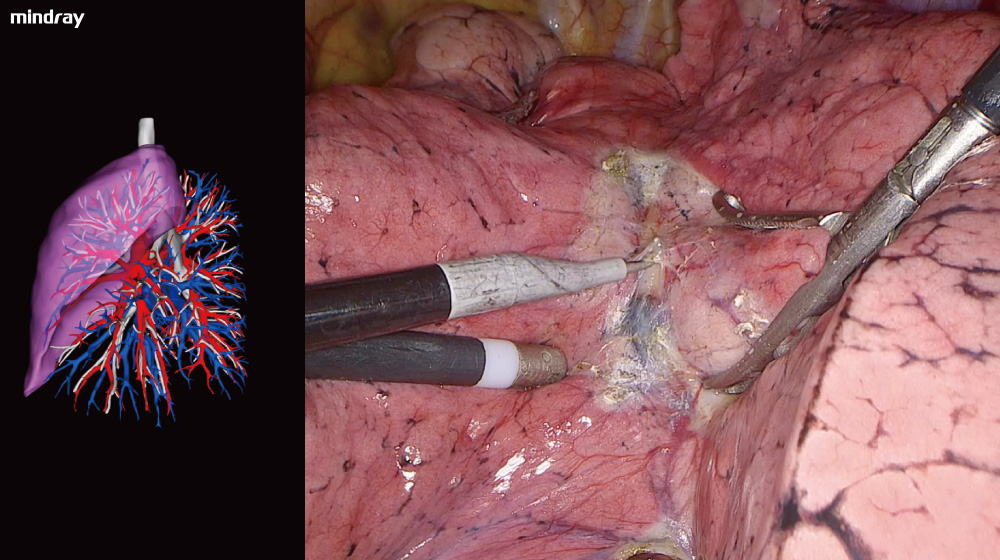

The endoscope can display a 3D reconstruction of the organs' structure, together with the surgical view on the same screen, to assist the surgeon with real-time correction needed during the procedure.